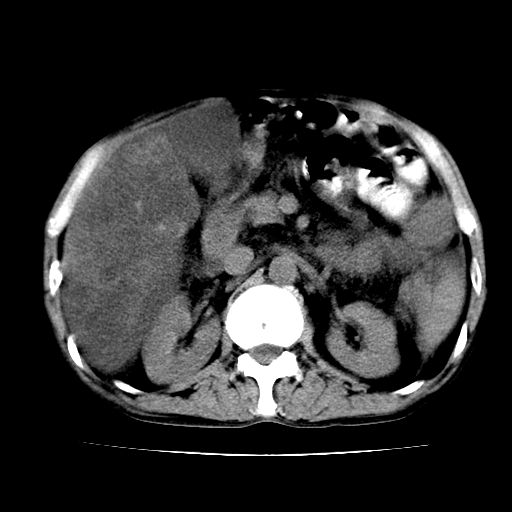

男,55岁,发现“肝硬化”5年,现腰疼、腹胀10余日,巩膜黄染、腹稍胀,肝肋下3指,质硬无压疼,移动性+,血生化:总胆、直胆、间胆均升高。

肝硬化,脾大,腹水

脂肪肝

肝内多发低密度灶(建议增强扫描除外肝癌)

肝脾肿大,脂肪肝,腹水。建议增强除外肝癌。

1.脂肪肝

2.腹水

3.肝脾肿大

4.肝癌?

建议增强